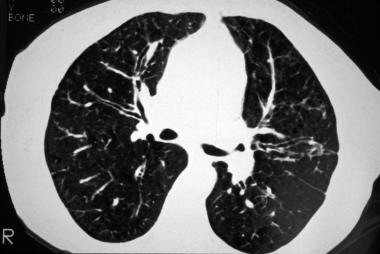

➢马赛克症是HRCT扫描中小气道异常的第二个征象,约64%的患者可见马赛克症。

➢支气管壁增厚,约48%-76%的患者可见支气管壁增厚。

图片

图7 支气管壁增厚